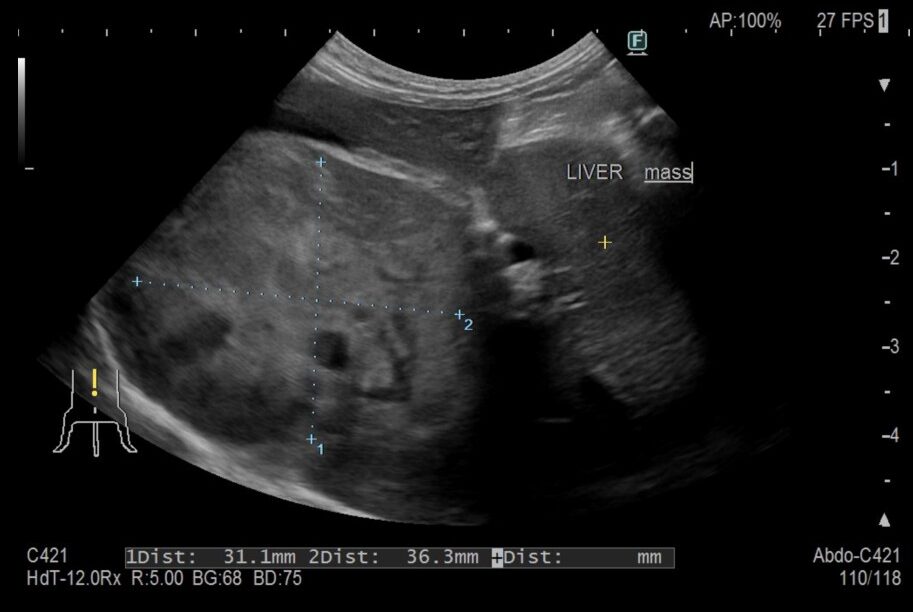

肝臓腫瘤